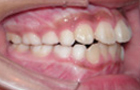

| 治療法 | 拡大装置にて上顎歯列の拡大を行い、機能矯正装置にて下顎位の是正、下顎の発育促進を行った |

横向き寝やうつぶせ、頬杖などに気をつけて治療をし、V字型だった歯並びが本来のU字型になってきました。

これで永久歯を抜かないで治療することができるようになりました。飛び出していた前歯がだんだん咬みあってきました。

まだまだ途中経過ですが、身体がだいぶんまっすぐになってきました。